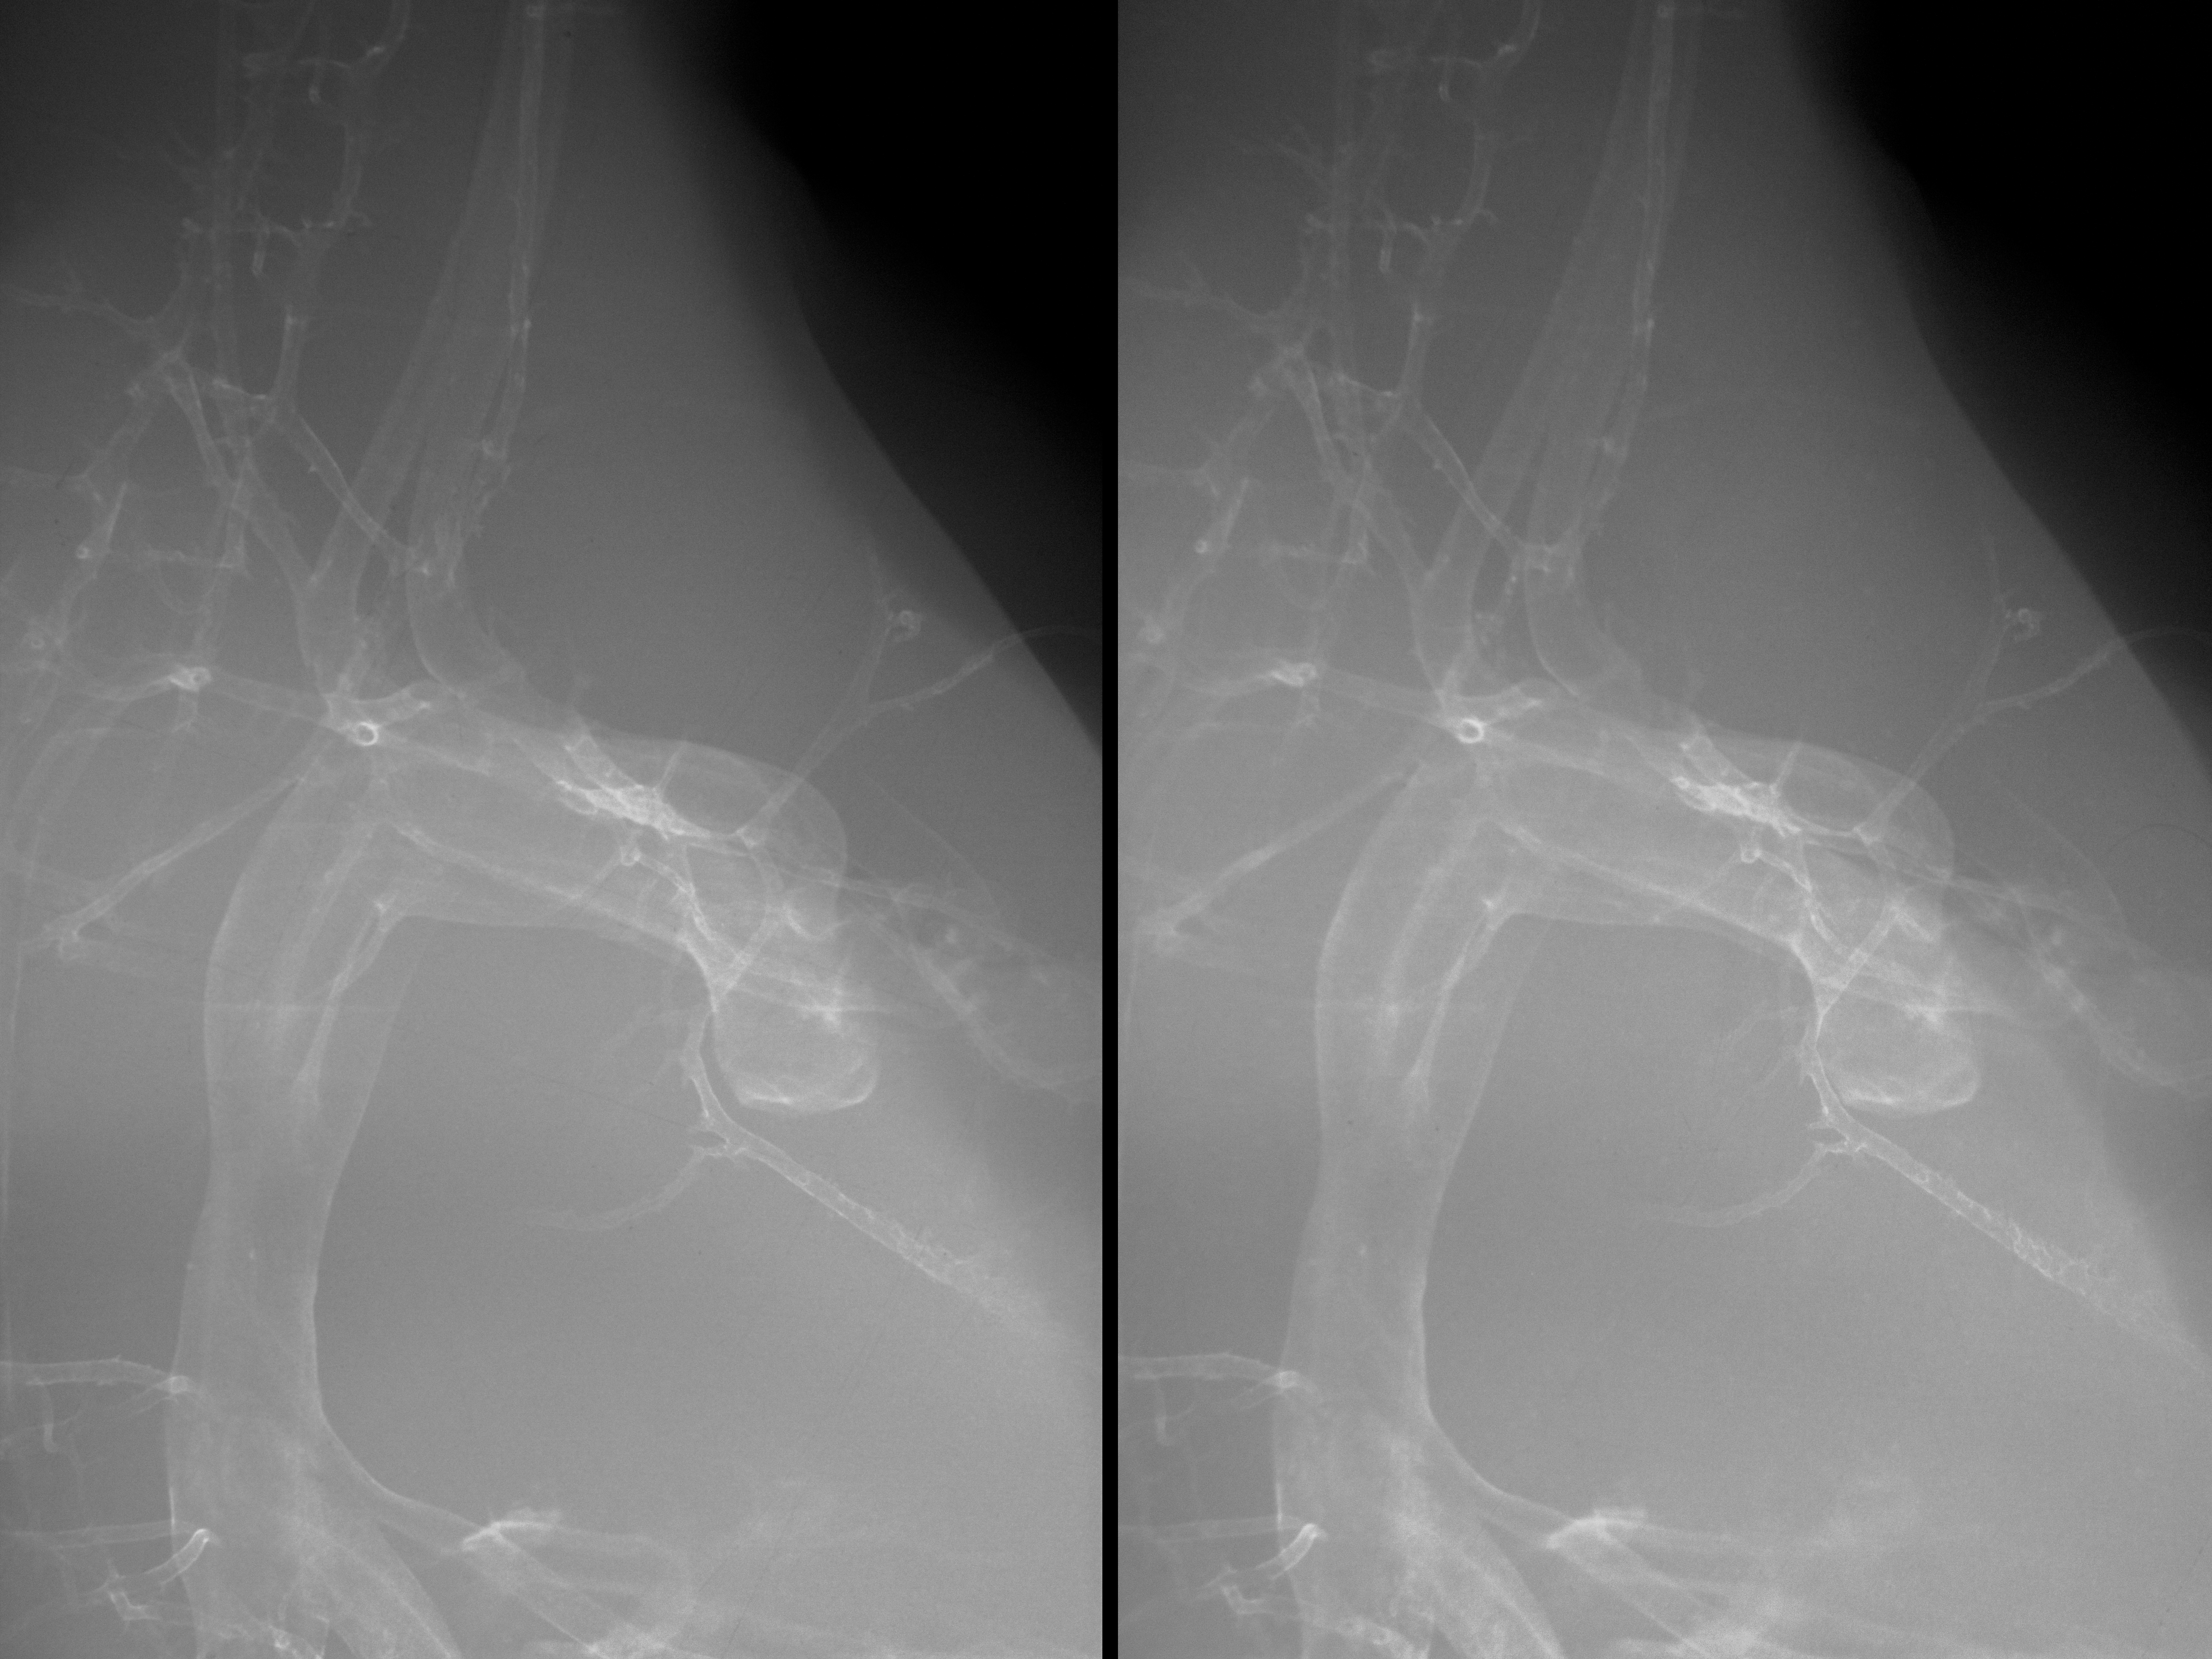

Chick Embryo Microangiography

Hamburger-Hamilton (HH) Stage 35 (approx. 8.5 - 9 days)

Stereo X-Ray Micrographs